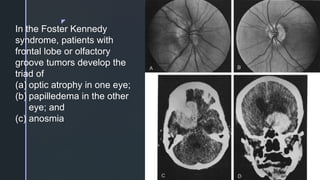

In the Foster Kennedy

syndrome, patients with

frontal lobe or olfactory

groove tumors develop the

triad of

(a) optic atrophy in one eye;

(b) papilledema in the other

eye; and

(c) anosmia

z In the FosterKennedy syndrome, patients with frontal lobe or olfactory groove tumors develop the triad of (a) optic atrophy in one eye; (b) papilledema in the other eye; and (c) anosmia

• #32Ā Foster Kennedy syndrome. A, The right optic disc shows mild papilledema. B, The left disc is pale, The optic nerve ipsilateral to the tumor is generally atrophic because of compression. Optic nerve compression prevents elevated intrasheath pressure and produces ipsilateral atrophy of optic nerve fibers